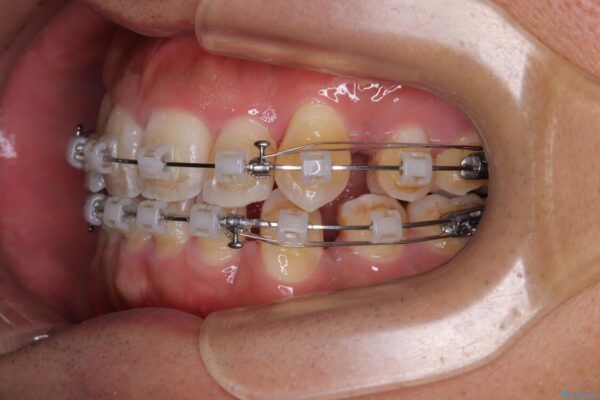

治療途中

• 八重歯と前歯のガタガタを抜歯矯正で治療|クリアブラケット使用例 治療途中画像

矯正装置は、審美性と費用面のバランスを考慮して、プラスチックブラケットとメタルワイヤーを使用しました。

透明感のあるブラケットを用いたため、従来の金属装置よりも目立ちにくく、日常生活での見た目の不安も軽減できます。